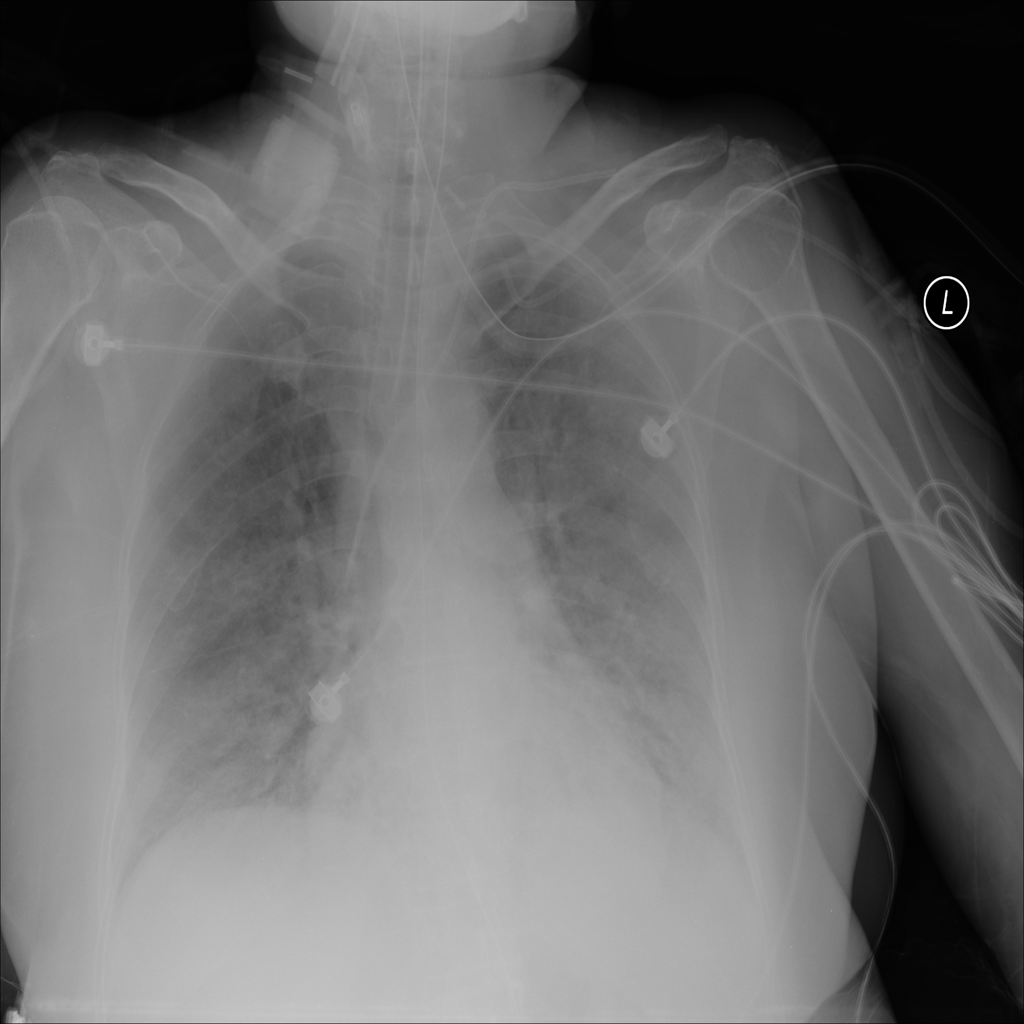

PAT-C1A7 · IMG-004Consolidation

PAT-C1A7 · IMG-004

PA